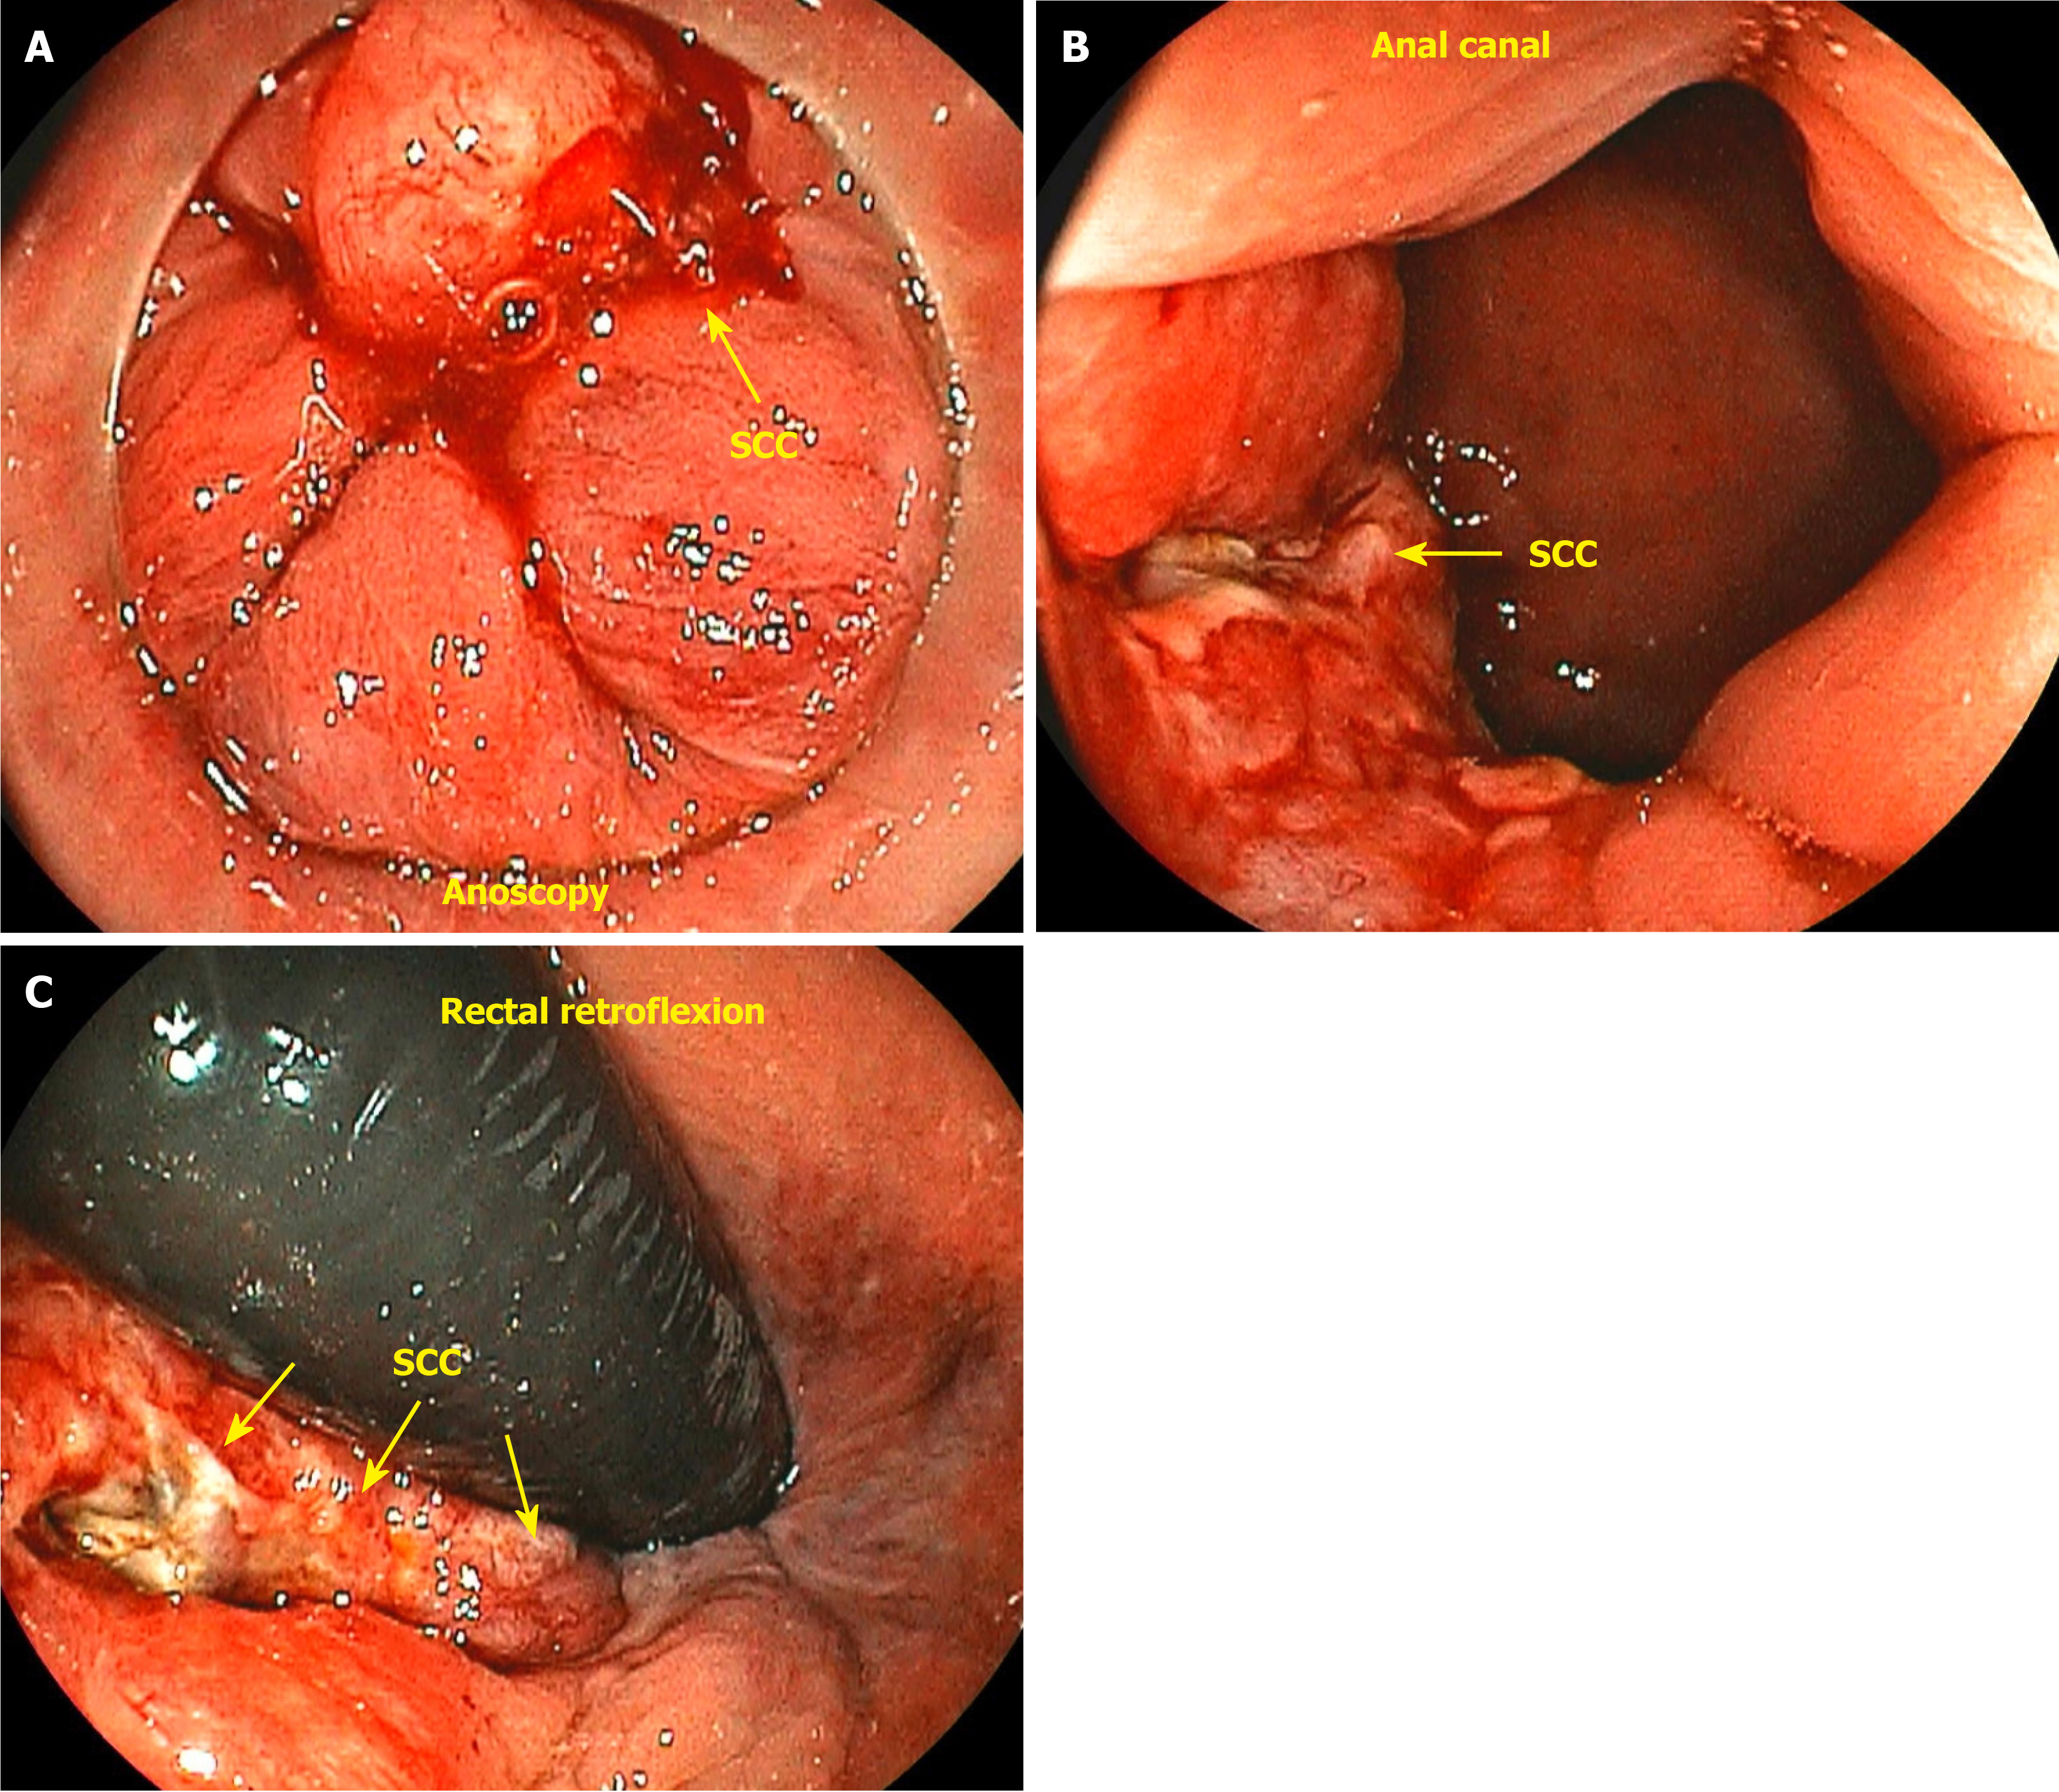

Anal cancer involves malignant growth in the anal canal and surrounding perianal region, including the anal margin. The anal canal spans the anorectal junction, approximately 1 cm above the pectinate line, to the anal verge, also known as Hilton’s white line, marking the boundary between the mucocutaneous and cutaneous zones. The anal margin extends 5 cm radially from the anal verge. The surgical definition of the anal canal is approximately 2-4 cm in length, bounded above by the end of the rectal mucosa and below by the perianal skin. The mucocutaneous junction between these two boundaries comprises the proximal transition zone and distal squamous epithelium (Figure 1). It is important to distinguish tumors arising within the anal canal from those originating in the perianal skin because of their differing biological behaviors and distinct treatment approaches[15]. Tumors located distal to the pectinate line are typically squamous cell carcinomas (SCCs) (keratinizing), also known as epidermoid or spinocellular carcinomas[16] (Figure 2).

Tumors located just proximal to the pectinate line are typically nonkeratinizing SCCs, also known as basaloid or cloacogenic carcinomas (Figure 3). Approximately 90% of anal SCCs are caused by infection with high-risk HPV[17]. Adenocarcinomas originate from the columnar epithelium found in the proximal part of the anal canal. SCC is the most prevalent type of malignancy of the anus, accounting for approximately 85% of all malignant lesions in this area[18]. The prognosis of carcinoma of the anal margin is generally better than that of tumors of the anal canal. This category of neoplasms includes SCCs, also known as epidermoid carcinoma, Bowen’s disease, Paget’s disease[19], basal cell carcinoma, and giant condylomata acuminata of Bushke-Löwenstein, a rare form of SCCs (Figure 4). Any suspicious lesion located around the anus should be biopsied. The confirmation of malignant neoplasia typically requires treatment with wide local excision. These lesions have a low propensity to metastasize[20].

This patient complained of bleeding during bowel movements, and a colonoscopy revealed a small, ulcerated lesion in the anal canal. A histological study revealed SCC (Figure 10A and B). Patients with HPV-related lesions can have their evaluation extended through the appropriate use of dyes and targeted biopsies, and lesions can be properly resected immediately without the need for a new appointment, which can take too long, thereby eliminating the chance of early cure. Many lesions are subtle, small, and challenging to identify. A thorough and close inspection is necessary to detect small nodules and distinct changes in the mucosa of the anal canal (Figure 10C and D). The colonoscopist can also collect material via brush cytology and request laboratory tests when there is a suspicion of an STI.